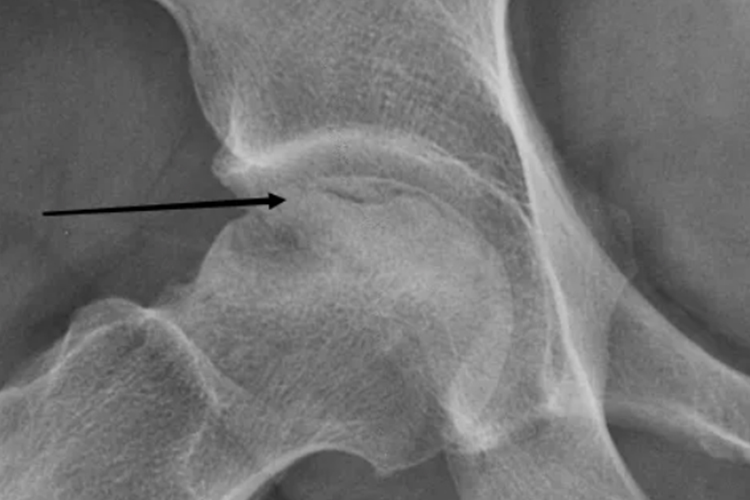

股骨头坏死新月征在X线片可示关节软骨下骨质中可见1-2cm宽的弧形透明带。

股骨头坏死新月征可见于股骨头坏死Ⅰ期X线,股骨头外形完整,关节间隙正常,股骨头负重区关节软骨下骨质中可见1-2cm宽的弧形透明带,构成“新月征”。此为坏死松质骨塌陷并与关节软骨分离的表现,这一征象在诊断股骨头坏死中有重要价值。